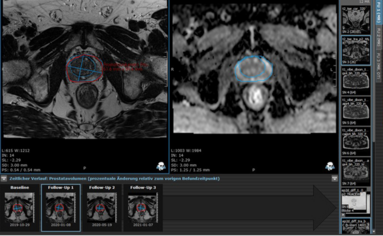

Advancing Neuro-Oncology Assessments: Mint Medical to Integrate Newly Published RANO 2.0 Criteria into mint Lesion™

Glioblastomas and other gliomas are the most common malignant primary brain tumor types, yet few effective therapies are available. Clinical research and clinical trials are essential in supporting…